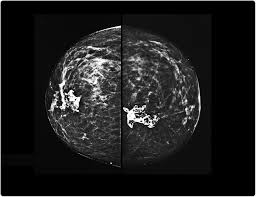

Abnormalities such as cancerous tumors usually appear brighter because they are denser. That makes it easy to detect abnormalities, which generally show up as white. It's so important to listen to the messages our bodies are telling. Ultimately, the news is good: A lump or tumor will show up as a focused white area on a mammogram.

A lump or tumor will show up as a focused white area on a mammogram. It appears to be developing in a concentric pattern. Ultimately, the news is good: These deposits show up as tiny white spots on a mammogram, and there may be only one or two, or too many to count, says jay baker, md, a breast imaging specialist at the duke cancer center.most people assume that what doctors are looking for on a mammogram are lumps, dr. However, when the breast is compressed from top to bottom, the tissue in the upper breast can overlap tissue in the lower breast. What does breast cancer look like on a mammogram? Any area that does not look like normal tissue is a possible cause for concern. Screening mammograms have been used since the 1980s.

Benign, noncancerous masses can appear as a focal asymmetry. Breast cancer can present either as an area of focal asymmetry or when advanced can even present as a new asymmetry in breast size. Images are displayed as a series of thin slices that can. The outer edges of these cells look fuzzy or spiky (called spiculated). What does breast cancer look like on a mammogram? Diagnostic mammograms involve taking more views than screening mammograms. What does breast cancer look like on a mammogram? Not all women have calcifications in their breasts—but most do. This is why you should always talk to your doctor if you notice an unexplained change in the size of a breast. Ultimately, the news is good: Rather than an image that is formed from pictures taken from top to bottom and side to side like a. Even if you have a lump in only one breast, pictures will be taken of both breasts. They will look carefully at the mammogram to interpret the results.